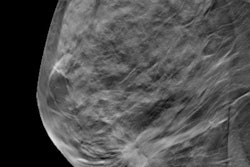

Full-field digital mammography (FFDM) detects breast cancer better than either analog film-screen mammography or computed radiography (CR), regardless of age, breast density, or screening round, according to a South Korean retrospective study of over 8 million women published online on December 3 in Radiology.

Over three years, a research team led by Dr. Seri Hong, PhD, from the National Cancer Control Institute at the National Cancer Center in Goyang, Republic of Korea, examined screening mammograms from the nationwide breast cancer screening program, which was linked with the national cancer registry. They found FFDM performed better than film-screen mammography and CR in screening accuracy and area under the curve (AUC) for the general female population.

Hong et al examined data acquired from the Korea-wide breast screening program for the period of January 1, 2011 to December 31, 2013. The study included 8,482,803 Korean women ages 40 to 79 who were screened biennially with film-screen mammography, CR, or FFDM. A little more than a third (34.4%) had analog mammography, 51.7% received CR, and 13.9% underwent FFDM.

In total, 13,616 detected breast cancer cases were included. FFDM demonstrated higher sensitivity and AUC but lower specificity, the authors found.